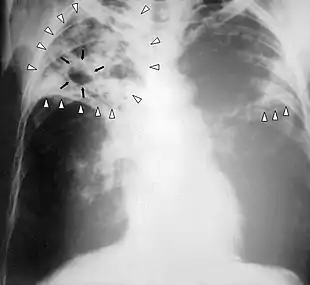

| Chest X-ray of a person with advanced tuberculosis: Infection in both lungs is marked by white arrow-heads, and the formation of a cavity is marked by black arrows. | |